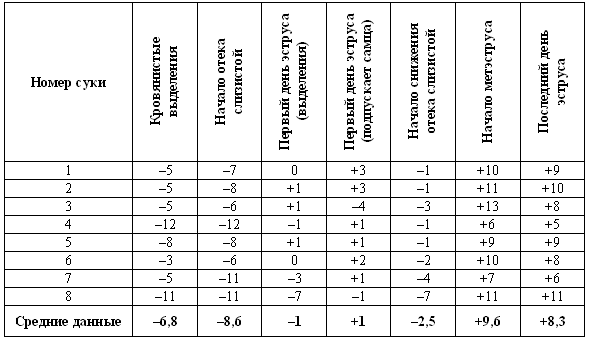

Табл. 1.1. Время проявления основных клинических признаков (по отношению к пику ЛГ) по данным наблюдения за 8 собаками.

Предполагаемый фертильный период — от 4-го до 7-го дня.

Примечания:

— кровянистые выделения появляются за несколько дней до начала эструса;

— самка подпускает к себе самца непосредственно перед началом фертильного периода;

— последний день восприимчивости может наблюдаться спустя несколько дней после окончания фертильного периода, т. е. в начале метэструса;

— начало уменьшения отека слизистой оболочки обычно наблюдается перед пиком ЛГ.